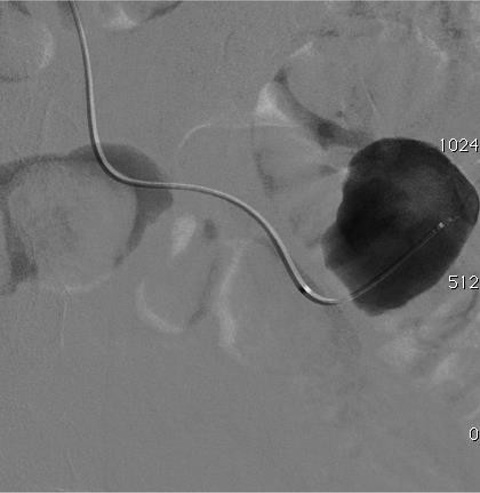

• 假性动脉瘤 False aneurysms

病例三:Front and back door  embolization with  Onyx

Cavity filling  Controlled sandwich  (Onyx+++)

Onyx